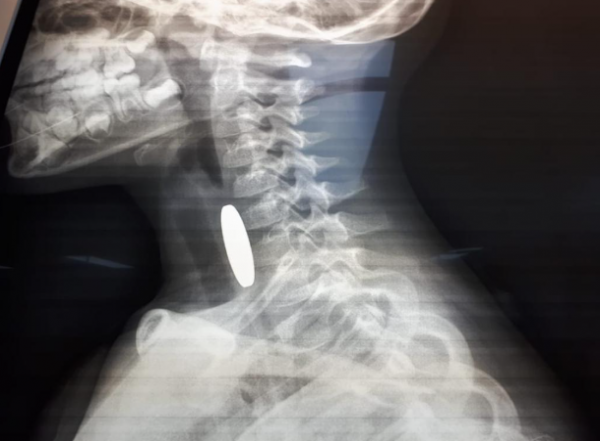

أخبار البلد -   - أنقذت مرتبات دورية نجدة تابعة لشرطة مادبا أثناء الوظيفة الرسمية حياة طفل يبلغ من العمر ثلاثة أعوام ونصف، بعد أن تعرض لحادثة اختناق إثر ابتلاع عملة معدنية في منطقة لواء ذيبان.

وفي التفاصيل، قال والد الطفل محمد الجديعات لإذاعة الأمن العام، إنه وبعد أن لاحظ أن طفله يجد صعوبة بالتنفس قام بشكل فوري بإسعافه باتجاه مستشفى الأميرة سلمى الحكومي، حيث صادف وجود دورية نجدة على مقربة من منزله وعلى الفور استنجد بهم، ليقوم أفراد الدورية بتقديم الإسعافات الأولية اللازمة باحترافية لمثل هذه الحالات بعد أن ابلغهم أنه قد ابتلع قطعه معدنية .